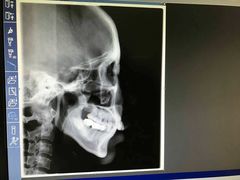

• TSK齿科德申会口腔门诊·联洋诊所

• -TSK齿科德申会口腔门诊·联洋诊所

金色罗盘 | 17-01-06

西瓜小菜菜的夏天 | 16-12-30